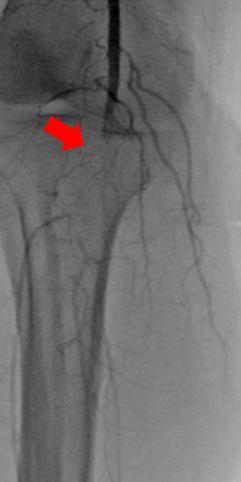

箭头所示:右腘动脉血栓栓塞,血流中断

术后右下肢动脉血流复通

箭头所示:左股、腘动脉血栓栓塞,血流中断

术后:左股腘动脉血流复通